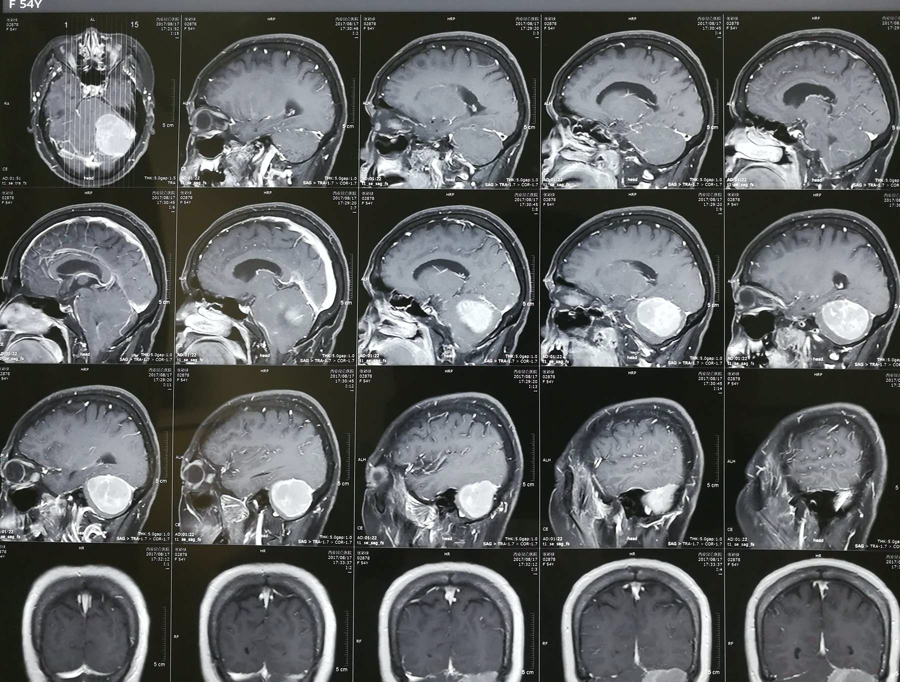

脑膜瘤严重吗?脑膜瘤起源于蛛网膜细胞,它们是覆盖大脑和脊髓的薄蜘蛛网状膜内的细胞,是常见的颅脑肿瘤...

脑膜瘤严重吗?虽然其多呈良性,但如不加以治疗,脑膜瘤会给脑部施加压力,并导致并发症。良性脑膜瘤能活多久?这取决于患者的具体治疗情况...

脑膜瘤 如何治疗不易复发?2016年美国脑肿瘤注册中心(Central Brain Tumor Registry of the United States,CBTRUS)统计,脑膜瘤约占颅内肿瘤的36.6%。根据国际卫生组织(World Health Organization,WHO)...